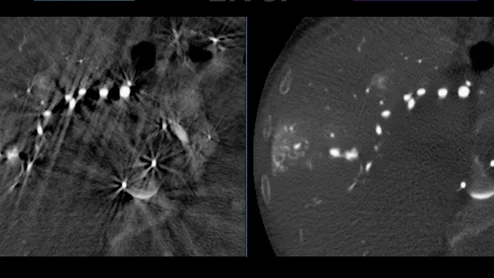

Calcified carotid plaques more likely to rupture than previously believed

Ruptured plaques can lead to the formation of blood clots that significantly increase the risk of stroke.